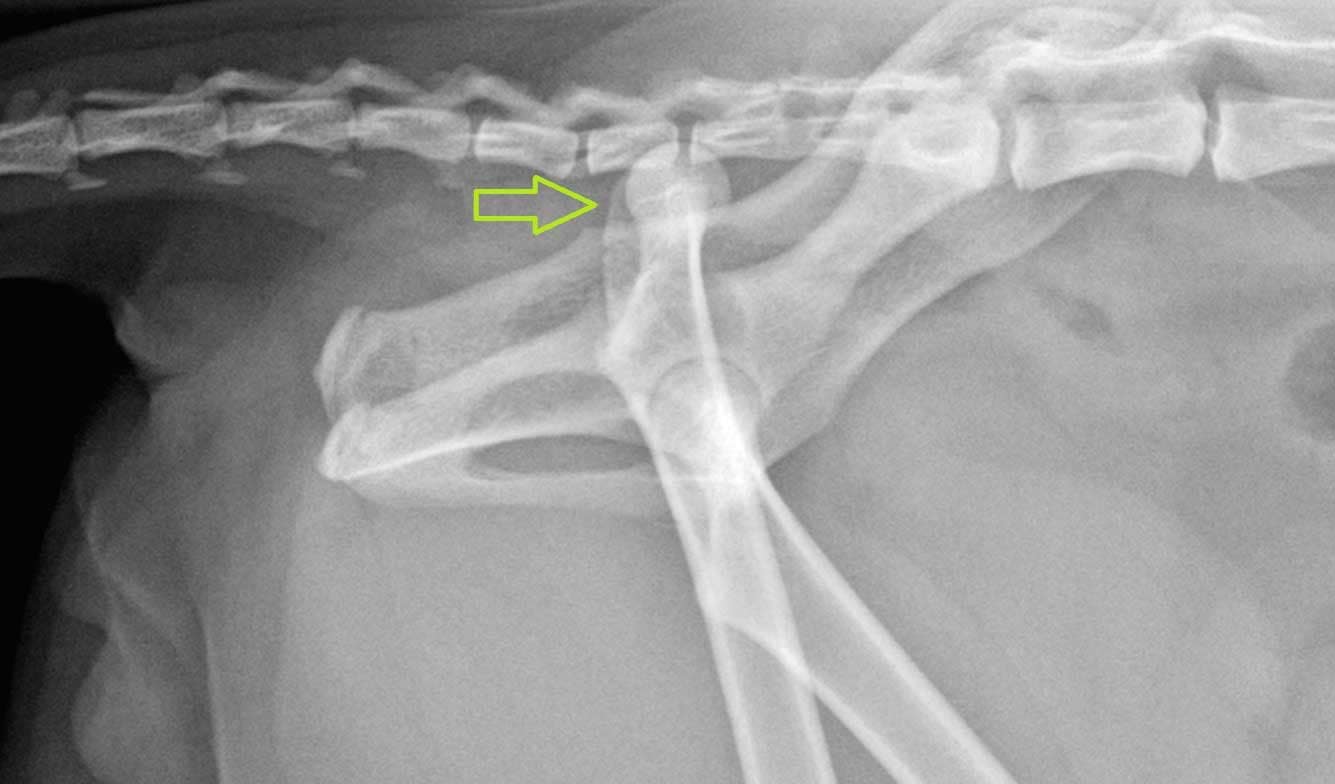

Hieronder is op een plastic model uitgebeeld hoe een bandje is aangelegd om de heup in de kom te houden.